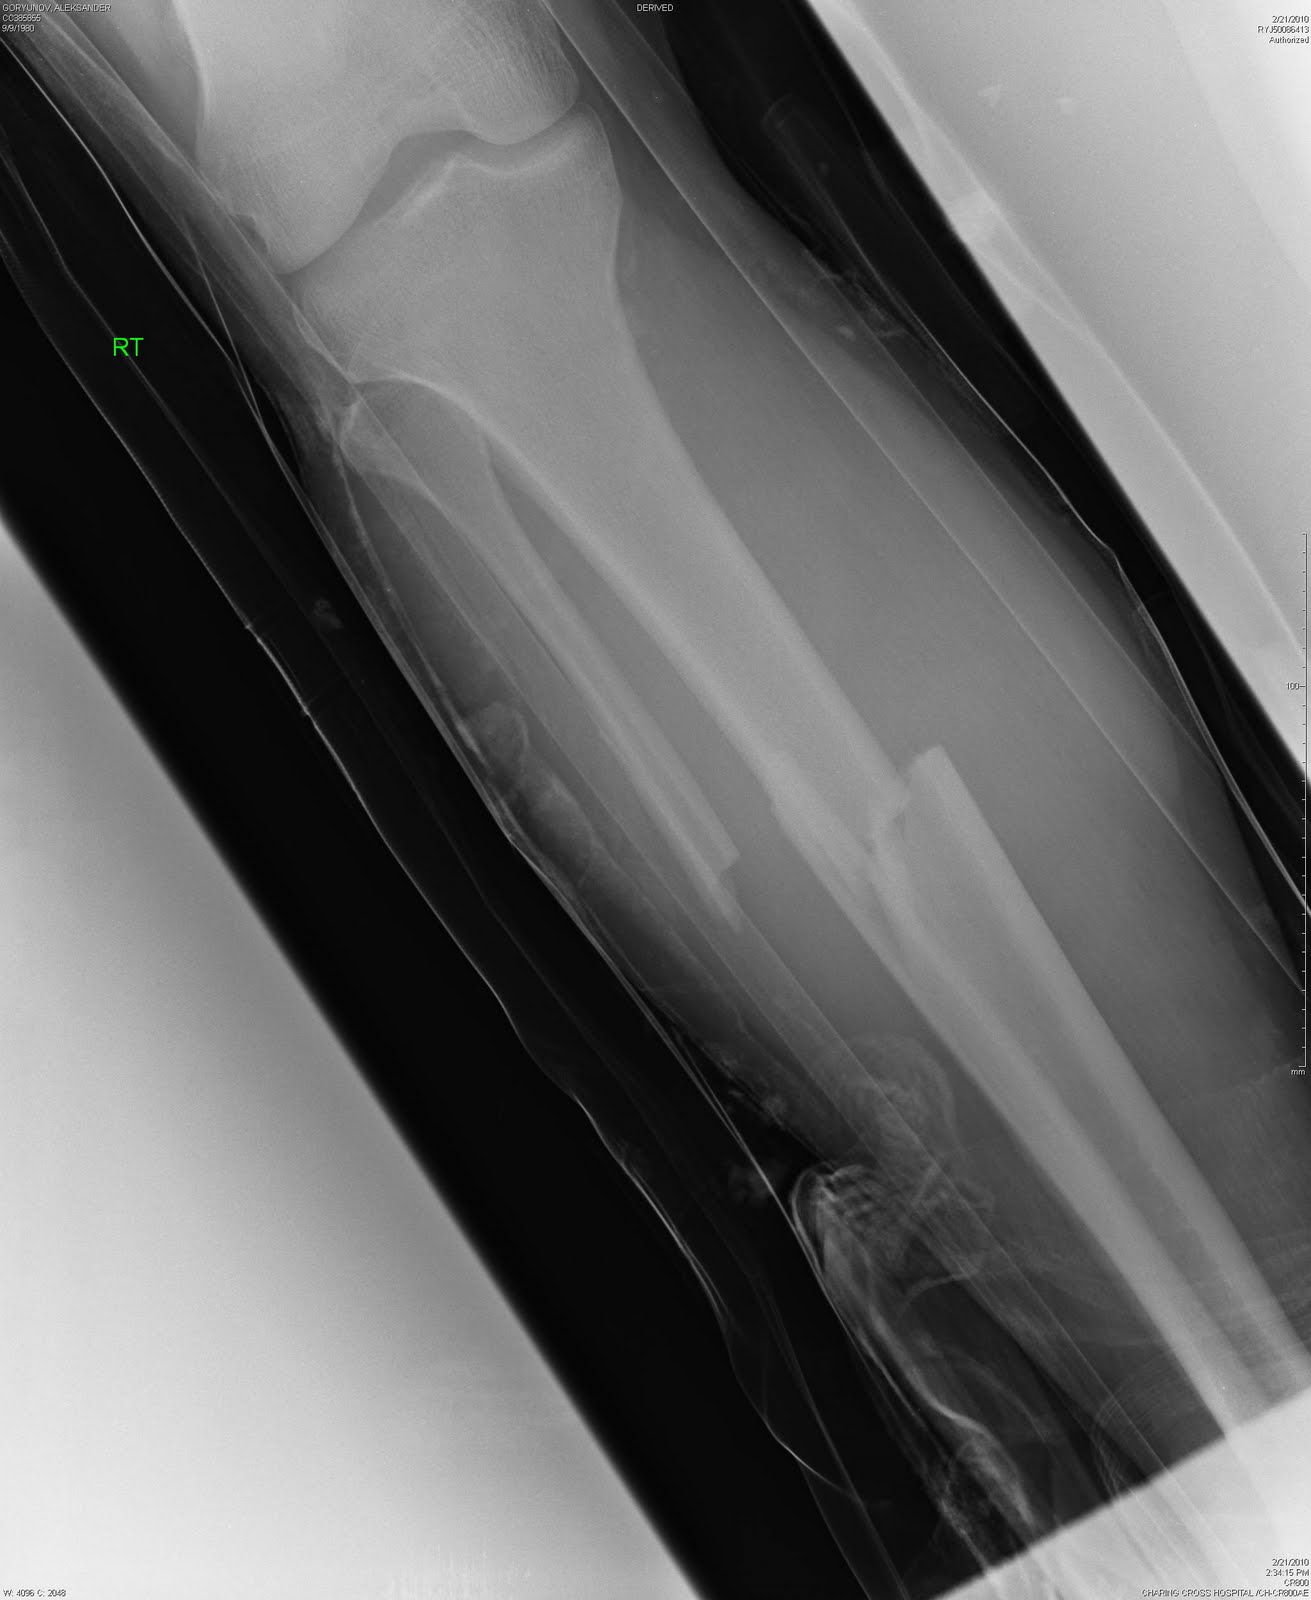

Перелом двойной - тибии и фибулы - закрытый, с клиновидным и сильно смещенным раздроблением тибии. Выглядит все это не очень, так что неудивительно, что мне он показан не был (увижу его только через месяц, когда на CD все рентгены пришлют домой).

Снимок еще раз подтвердил, что мне повезло - гетра с колготками (да, зимой иногда пододеваю к всеобщему смеху колготки - ноги в тепле, проблем с мышцами меньше) каким-то образом удержали ногу после сильнейшего удара и кость не пробилась наружу. Конечно, с другой стороны не повезло - сьехал щиток и оголил ногу в этом месте – но... бывает, а могло быть и хуже.

После изначального вправления, все это стало выглядеть вот так.